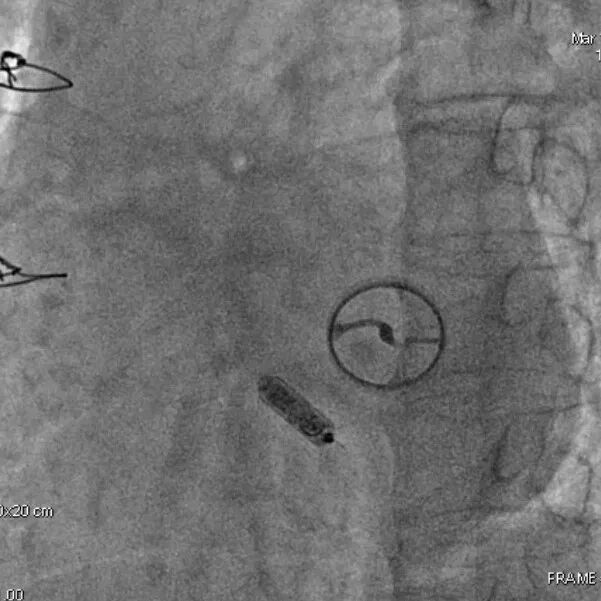

2015年,中国医学科学院阜外医院参与了Micra全球上市前临床试验,总共入组了5名患者。该临床试验为全球多中心、非随机、单臂上市前临床研究,旨在评估Micra VR无导线起搏器的安全性和有效性。该项研究的结果发表在2015年新英格兰医学杂志上,研究结果表明,Micra VR无导线起搏器手术成功率为99.2%,其不良事件发生率相对于传统起搏器降低了48%。

Micra无导线起搏器自2015年3月在国内首次使用于临床,中国最早获益于无导线疗法的患者在长达十年的随访周期内,展现出了优秀的长期电学参数表现。其中阈值、阻抗、感知都在正常范围以内,起搏器寿命也达到预期。无导线起搏器为患者提供了长久、安全、可靠的治疗选择。随着临床应用的增多和使用时间的延长,相信有更多临床数据可以说明无导线起搏器在中国患者中的安全性和有效性。